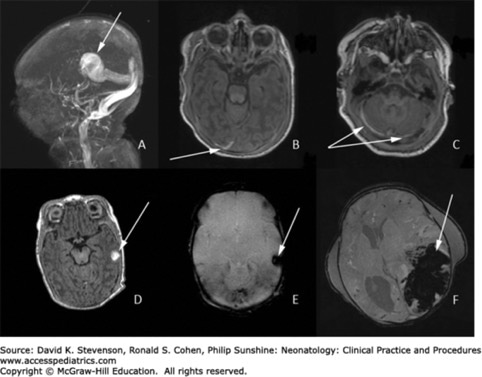

Answer: Intracranial hemorrhage. A, Magnetic resonance venogram (MRV) of a vein of Galen malformation with widely dilated venous system. B, T1 image with subdural hemorrhage (SDH) shown in the right occipital lobe (see arrow). C, SDH in the posterior fossa (see arrows). Image D reveals a small left-sided intraparenchymal hemorrhage (IPH) caused by a presumed cortical vein thrombosis that is characteristically hyperintense on T1. Image E shows this same hemorrhage with blooming artifact on a susceptibility-weighted image (SWI). Finally, image F shows a massive left-sided IPH (blood is dark on SWI) with midline shift, leading ultimately to herniation in this unfortunate neonate.